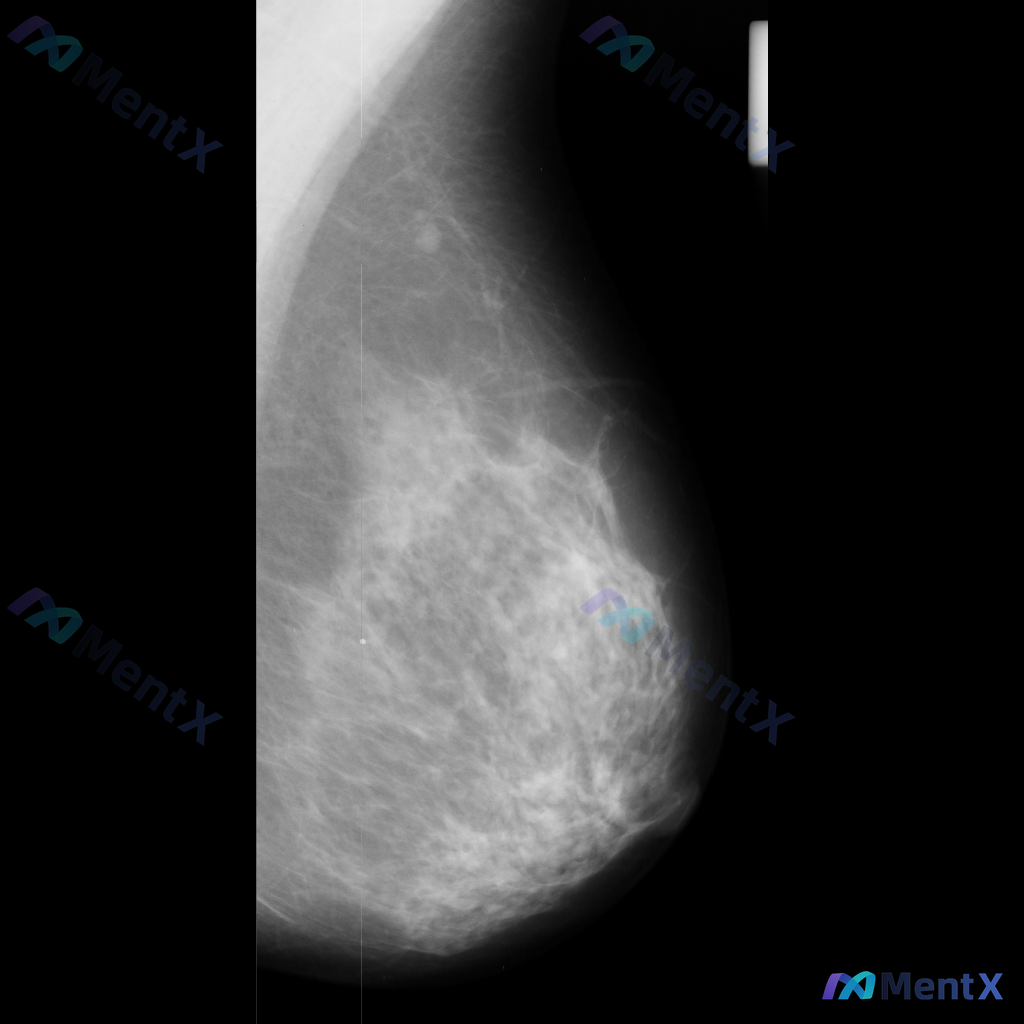

- 单侧乳腺X光片,投照体位考虑可能为内外斜位(MLO)

- 乳腺组织构成:不均匀致密型

- 影像质量:曝光适中,清晰度良好,无明显伪影

- 可见结构:皮肤、皮下脂肪层、乳头乳晕、Cooper韧带显示尚可;未见明确钙化血管或腋窝淋巴结

在乳腺上部区域,可见一个或两个密度较高的结节影:

- 其中右上方一枚结节密度较高,呈圆形或卵圆形

- 整体边界似乎相对清晰,但因腺体致密+仅单张影像,精确形态/边缘特征待明确

- 未见明确簇状或可疑钙化,未见明显结构扭曲

- 无双侧对比,无既往片对照